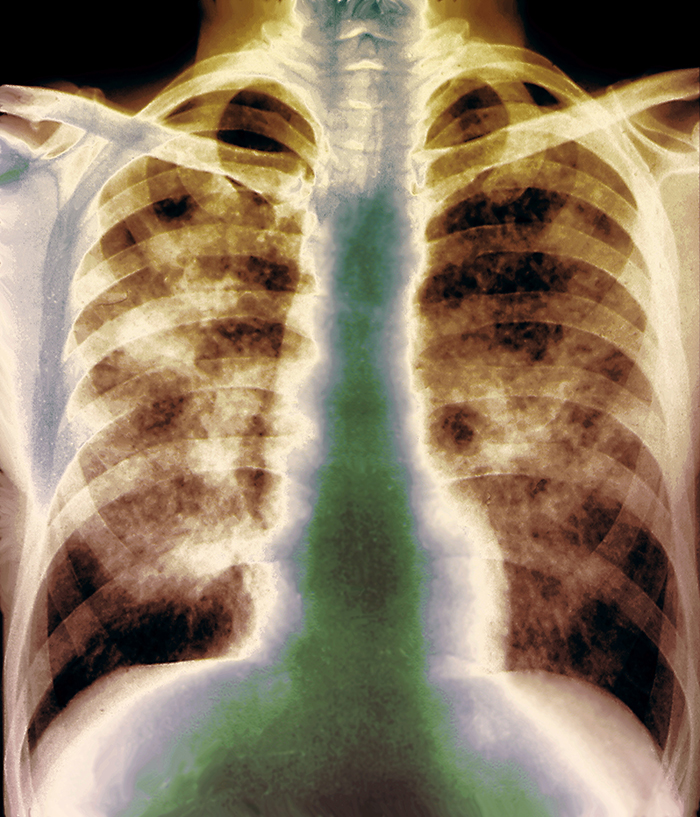

Luftvägssjukdomar med stark koppling till arbetslivet, men som är mindre vanliga, är bland annat silikos, allergisk alveolit och mesoteliom. Det finns en risk för att kunskapen om dessa sjukdomar håller på att försvinna, inte minst bland röntgenläkare.

Silikos orsakas av kvartsdamm, och drabbar bland annat dem som arbetar inom gruv- och stenindustrin, med att spränga berg eller anläggningsarbeten. I en färsk studie som presenteras i det här numret av Läkartidningen konstaterar Bengt Järvholm och Magnus Svartengren att arbetsmiljö i Sverige fortfarande kan innebära en risk för allvarlig silikos.

Maria Albin är i dag professor och överläkare vid Centrum för arbets- och miljömedicin i Stockholm läns landsting. 2005 larmade hon Arbetsmiljöverket om att hon fått in två konstaterade och ett misstänkt fall av silikos. Då granskade hon i efterhand röntgenplåtar och upptäckte att en patient hade gått runt med lungförändringar i 25 år.

»Dagens röntgenläkare kan inte urskilja silikos. Därför måste ett antal specialtränas, annars måste bilderna skickas utomlands för granskning«, sa Maria Albin i en artikel i tidningen Arbetsskydd 2006.

– Röntgenbilderna ingår ju i obligatoriska hälsokontroller som görs på dem som är exponerade för kvarts. Men hur bilderna ska granskas för att säkra kvaliteten har hamnat mellan stolarna. Arbetsmiljöverket fann att det inte var deras fråga, utan Socialstyrelsens, numera Folkhälsomyndighetens, fråga. Och såvitt jag vet är det fortfarande en ostandardiserad rutingranskning som görs, det vill säga de granskas inte av någon som fått särskild träning i att diagnostisera silikos och andra pneumokonioser, och man använder inte heller de referensbilder som finns för att få en standardiserad bedömning.

– Nej. Inte på den sidan. Det som däremot har hänt som skulle kunna underlätta är att annan diagnostik än vanlig slätröntgen har blivit mer tillgänglig. Man har kommit ned i stråldoser och har bättre upplösning. Så möjligheten finns att med ny teknik skärpa diagnostiken. Kanske har tiden verkat för att man kan hitta enklare lösningar, säger Maria Albin.